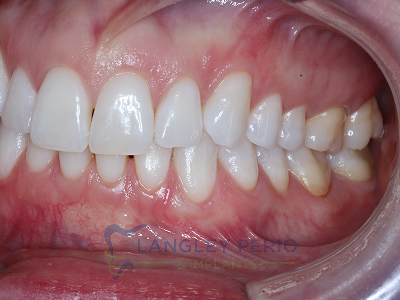

Case 2

Connective tissue grafting was done to cover exposed root surfaces to help to prevent root cavities from developing and reduce temperature sensitivity.